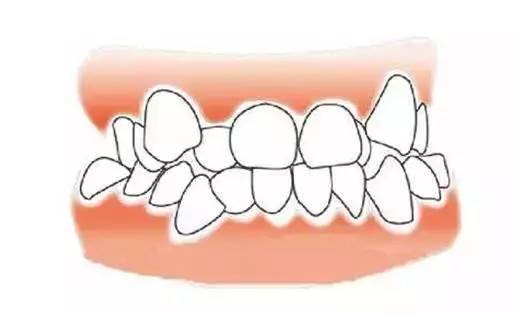

反颌(地包天)矫正

jpg,400x500,39209b

牙齿拥挤

jpg,400x300,20160b